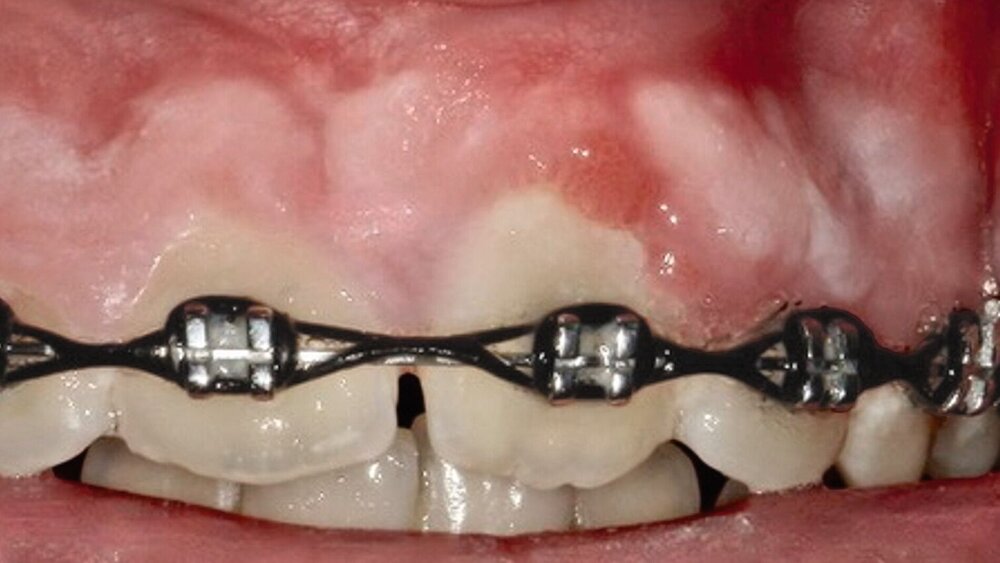

Ein zwölfjähriger Patient wurde von einem niedergelassenen Fachzahnarzt für Oralchirurgie zur operativen Entfernung einer unklaren Raumforderung im Oberkiefer überwiesen. Anamnestisch bemerkenswert war, dass Zahn 21 im Jahr 2023 durch den überweisenden Kollegen aufgrund einer begonnenen kieferorthopädischen Behandlung freigelegt wurde. Ein Jahr später zeigte sich bei der klinischen Untersuchung eine nicht-druckdolente, nicht-verschiebliche Vorwölbung der vestibulären Schleimhaut im Bereich 21-22 (Abbildung 1). In der angefertigten Digitalen Volumentomografie (DVT) ließ sich in dieser Region eine monolokuläre, relativ scharf begrenzte, radioluzente Struktur mit zentraler, diffus gefleckter Radioopazität erkennen (Abbildung 2).